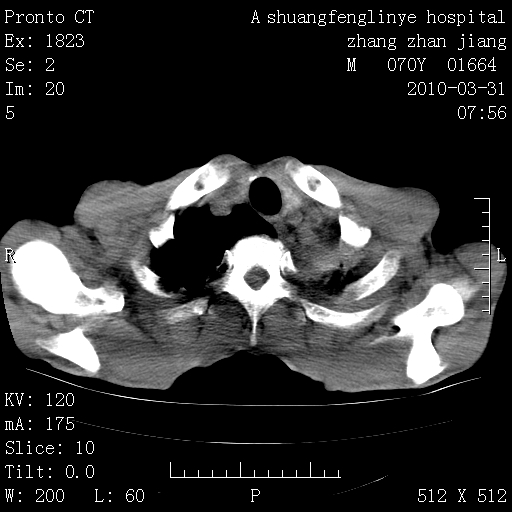

双上肺继发型tb并左上空洞形成,主动脉冠脉钙化。

1)两肺上叶继发性肺结核并左肺上叶空洞形成。2)冠状动脉及主动脉钙化。